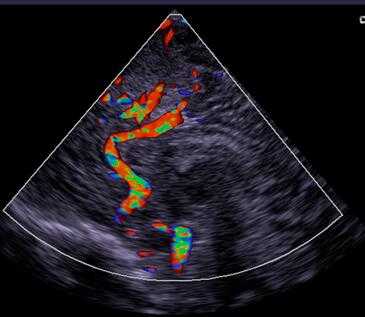

彩超是彩色多普勒超声的简称。它是根据多普勒效应在二维超声显像(即B超)的基础上,叠加彩色血流信号,实现彩色血流显像的一种方法。

多普勒超声诊断主要分为图谱多普勒、彩色血流成像、彩色能量成像。其中,以彩色血流成像最常见。

彩色血流成像就是基于血流的多普勒效应来成像的。(多普勒效应:当声源或接收体或两者同时相对介质运动时,接收体接收到的声波频率发生变化的现象。)

超声探头发出频率为f1的超声波,被流动的红细胞以更高或更低的频率f2反射回探头,根据频率的差异,使用相关技术可算出血流速度和方向等信息。

在上述机制图中,后续的编码和显像就是将储存的血流数据转换为色度信号,即上色。但上色可不是随心所欲的哦!

关于颜色的选择可是有严格的规定的,现在通用的是国际照明委员会规定的三原色:红、绿、蓝。

其他颜色都是由这三种颜色混合而成,如流向探头的血流出现湍流,将出现红色加绿色形成的黄色,流离探头的血流出现湍流,将出现蓝色加绿色形成的青色。